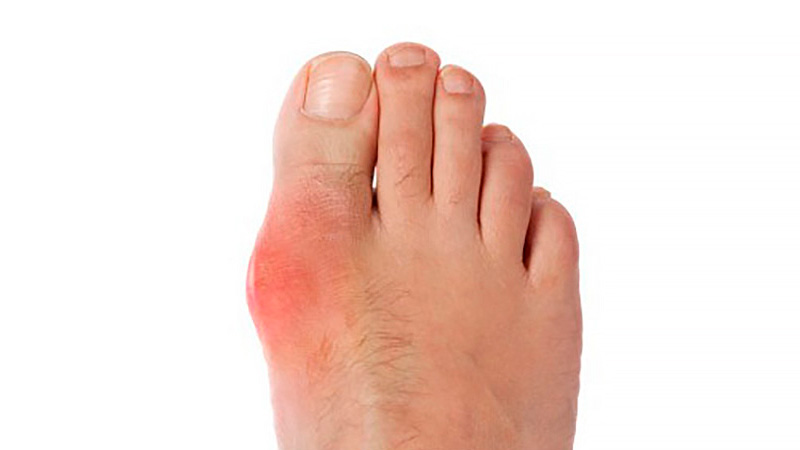

En pacientes con gota y sin enfermedad coronaria, el uso prolongado de alopurinol protege contra el primer síndrome coronario agudo (SCA) en comparación con los no usuarios. Por el contrario, los iniciadores del alopurinol, que posiblemente tenían más inflamación sistémica, tenían un mayor riesgo de SCA por primera vez en comparación con los usuarios a largo plazo. BMJ Open, 27 de febrero de 2025

En este estudio de cohorte poblacional, los pacientes diabéticos de tipo 2 tratados con metformina que iniciaron un inhibidor de SGLT-2 tuvieron menor frecuencia de crisis gotosas que aquellos a los que se agregó sulfonilureas. Estos resultados ayudan a guiar la selección de la terapia hipoglucemiante en pacientes con diabetes tipo 2 con riesgo de gota o que ya la padecen. JAMA Internal Medicine, 15 de abril de 2024.

En este ensayo clínico aleatorizado una intervención dietética intensiva fue segura y redujo eficazmente el peso corporal en personas con obesidad y gota, pero la pérdida de peso no se tradujo directamente en efectos sobre el nivel de uricemia, la fatiga, el dolor ni las exacerbaciones agudas de la gota. Arthritis & Rheumatology, enero de 2024.

En este estudio retrospectivo de pacientes con antecedentes de gota, los niveles de urato sérico al inicio del estudio se asociaron con el riesgo de brotes de gota posteriores y las tasas de hospitalización por gota recurrente. Estos hallazgos respaldan el uso de un nivel inicial de urato sérico para evaluar el riesgo de gota recurrente durante casi 10 años de seguimiento. JAMA, 6 de febrero de 2024.

En este estudio observacional se comparó el inicio de alopurinol para la gota acompañado de profilaxis con colchicina o con AINE versus alopurinol sin profilaxis asociada. Los eventos adversos fueron más comunes cuando se inició alopurinol con profilaxis, particularmente la aparición de diarrea con el uso de colchicina. Otros eventos fueron poco comunes, lo que brinda tranquilidad a los pacientes y a los médicos para permitir la toma de decisiones compartida. Annals of the Rheumatic Diseases, octubre de 2023.